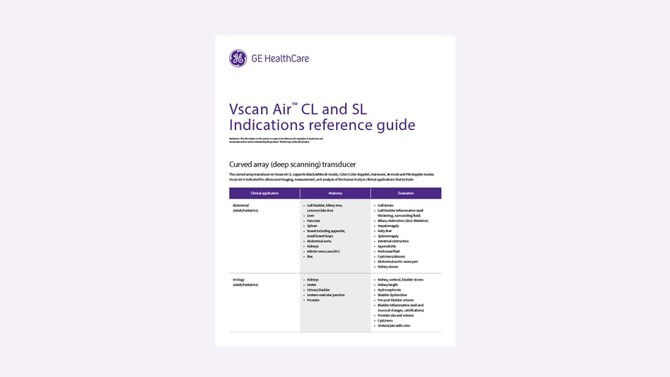

Curved array: Abdominal (Adult/Pediatrics), Urology (Adult/Pediatrics), OB/GYN, Lung/Thoracic (Adult/Pediatrics), Cardiac and hemodynamic assessment, Musculoskeletal (Conventional) (Adult/Pediatrics, Procedure guidance (Adult/Pediatrics).

Linear array: Peripheral Vascular, Lung/Thoracic (Adult /Pediatric), Small organs (Adult/Pediatric), Musculoskeletal — (Superficial and conventional) (Adult/Pediatrics), Nerves (Adult/Pediatrics), Neck and airway (Adult /Pediatric), Procedural guidance (Adult/Pediatrics), Ophthalmic*, Cephalic (Neonatal).

Check out our Indications for Use to see various exams that you can perform with Vscan Air.